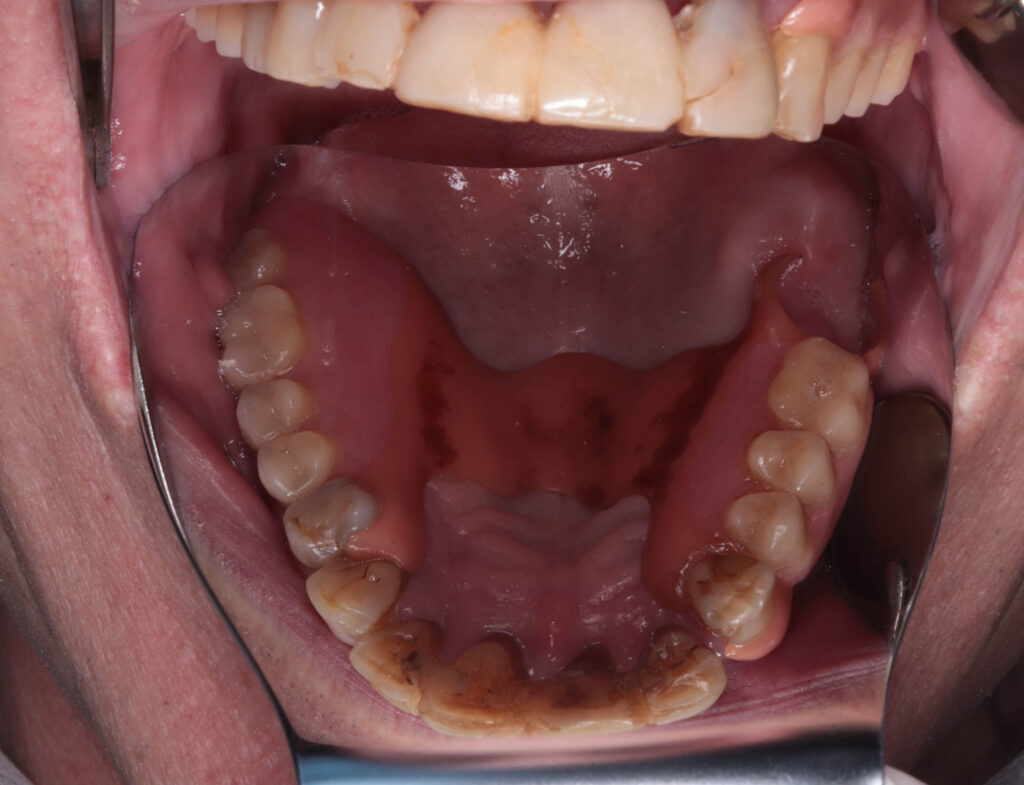

Ситуация до лечения

пациент до имплантации